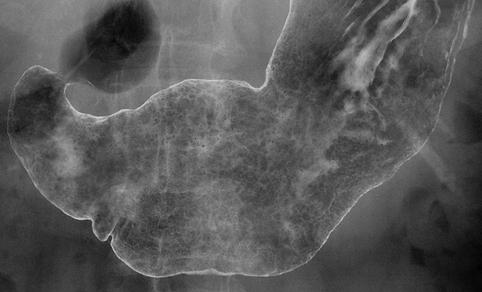

症例提示(所在地,施設名等): 鹿児島県・ 九州循環器病センター (Dr.下野)

疾患(病理主体)の分類悪性上皮性腫瘍/腺癌

部位(臓器別)胃(部位)/2つ以上

検査方法X-P

腫瘍の肉眼分類0型(表在型)/IIb型(IIb+IIc)

病変の最大径(ミリ)40以上

腫瘍の深達度m